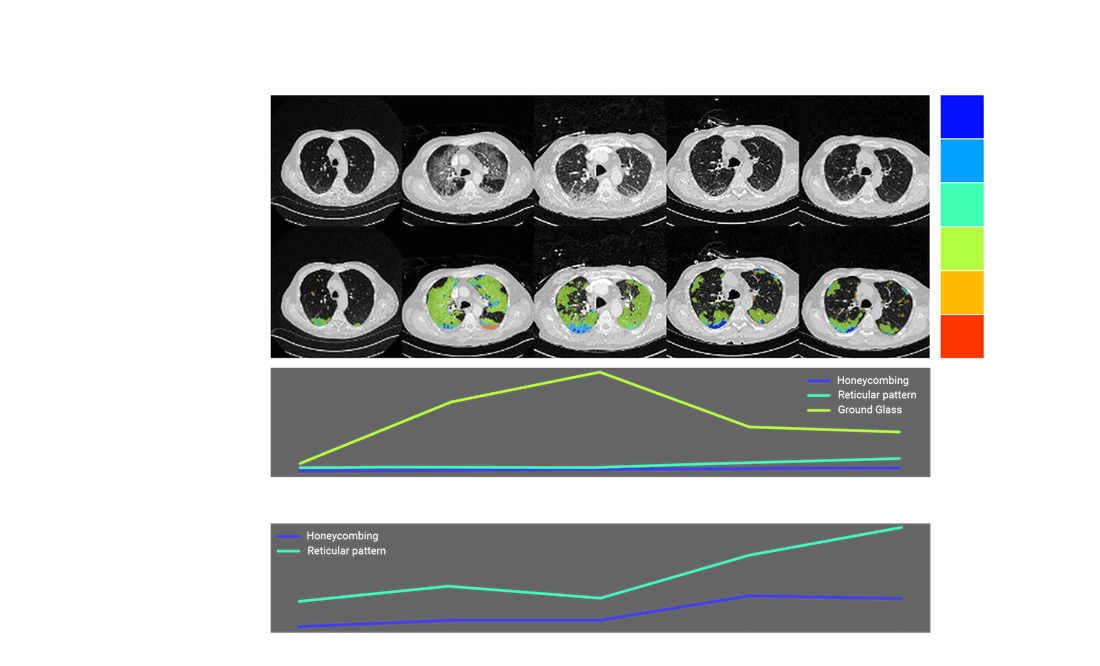

Learn how early-stage interstitial lung abnormalities (ILAs) detected in routine screenings can prevent progressive fibrotic lung disease. Discover the latest features of the OSIC Cloud platform, including advanced visualizations that highlight subtle lung changes, and hear vital insights from the Czech Republic’s national lung cancer screening program.

Discover how we can detect fibrotic lung disease before it becomes visible. Learn how AI and advanced imaging technologies are transforming pulmonary medicine. Explore the features of OSIC’s global data platform, which now houses over 7,000 fibrosis lung disease scans, and find out how these advancements facilitate earlier interventions for high-risk patients.

Training AI to Detect ILA

Can we predict which ILAs will progress to ILD?

OSIC is enabling researchers to train deep learning models to do just that.

• Early ILA detection using LDCT and HDCT

• Stratification of “at-risk” populations

• Potential for earlier treatment and better outcomes

AI + OSIC = New frontiers in preventive pulmonology

Unlocking Early Detection with AI ILA Risk Scoring

Enabling precision-driven, personalized management; minimizing missed and delayed diagnoses; enhancing outcomes through timely intervention.